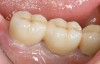

Figure 16  Replacement of the maxillary lateral incisor with a CAD/CAM zirconium abutment and a zirconium/ceramic crown.

Figure 16